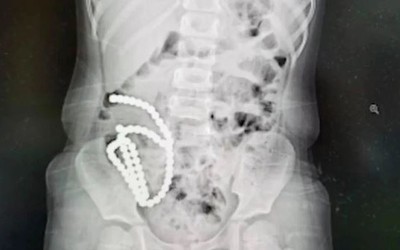

Bất tỉnh vì đau bụng, bác sĩ lấy ra thứ đáng sợ trong bụng bé gái

Tự nhổ tóc và nhai khi còn nhỏ, cô bé 9 tuổi đã phải trải qua ca phẫu thuật kéo dài 4 giờ để lấy búi tóc ra khỏi dạ dày.